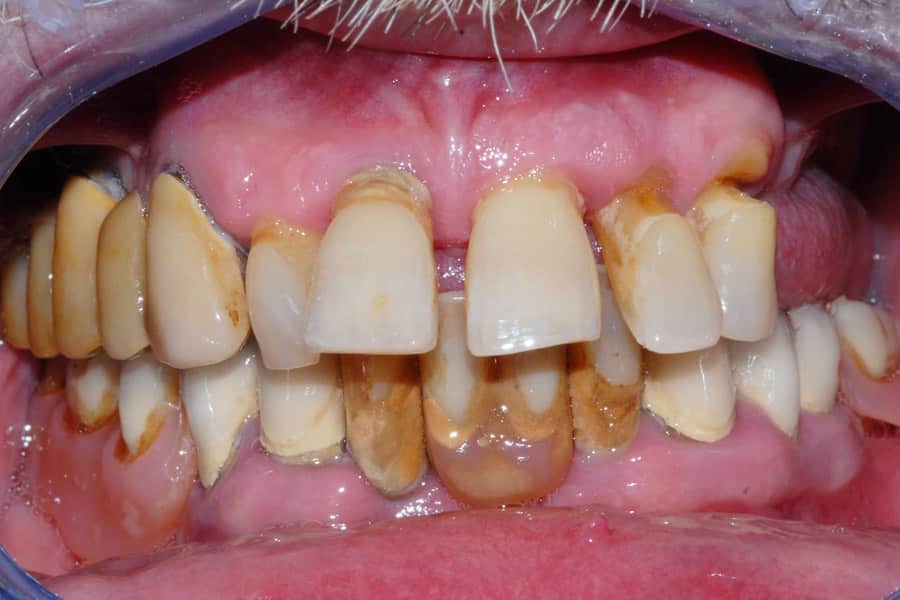

Abbiamo deciso di iniziare le cure dall’arcata superiore. In questa zona, la malattia aveva causato un forte ritiro delle gengive e la formazione di spazi profondi (tasche parodontali), portando allo spostamento dei denti anteriori. La situazione era così compromessa che è stato subito chiaro come non fosse possibile salvare i denti naturali.

Marco aveva una richiesta molto chiara: voleva evitare la tecnica “All on 4” e non desiderava avere una finta gengiva artificiale.

In casi clinici così complessi, la soluzione più comune proposta da molti studi è proprio l’All on 4. Questa tecnica prevede l’estrazione dei denti e la rimozione di una parte dell’osso rimasto per fare spazio a una protesi che include una gengiva finta.

La filosofia della nostra Clinica, tuttavia, è orientata verso una chirurgia che rispetti l’anatomia del paziente. Negli interventi post-estrattivi cerchiamo di evitare le procedure più invasive. Per questo motivo, anche in una situazione difficile come quella di Marco, abbiamo scelto il nostro protocollo di chirurgia mini-invasiva. L’obiettivo principale era permettere ai nuovi denti fissi di uscire direttamente dalla sua gengiva naturale.